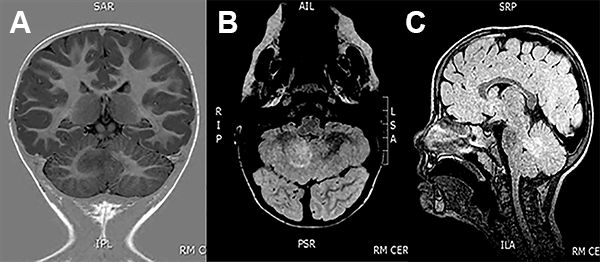

A los 3 años de vida se realizó un abordaje suboccipital telovelar con una exéresis macroscópicamente total de la lesión con buena evolución post operatoria (fig. 2).

Figura 2: Caso 1 Imágenes postquirúrgicas.

EEG de scalp normal. La RMN de encéfalo mostró una lesión expansiva en la profundidad del hemisferio cerebeloso derecho, en contacto con el pedúnculo cerebeloso superior, con mínimo efecto de masa y sin realce con el contraste (fig. 3).

Figura 3: Caso 2. Imágenes preoperatorias.

A los 29 meses de edad se realizó una exéresis subtotal de la lesión a través de un abordaje suboccipital telovelar (fig. 4). Durante el procedimiento se realizó elecrocorticografía (ECoG), con un electrodo profundo colocado bajo guía ecográfica intraoperatoria que no mostró patrones patológicos. La experiencia en ECoG cerebelosa es escala o nula, por lo tanto se hace muy difícil su interpretación(fig. 5).

Figura 4: Caso 2. Ecografia intraoperatoria.

Figura 5: Caso 2. Imágenes postoperatorias.